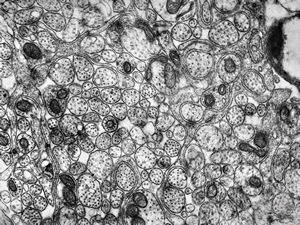

F,50y. | progressive multifocal leukoencephalopathy- viral particles in a glial cell